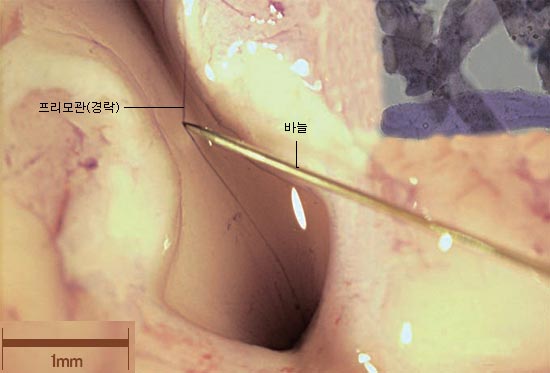

韩国中央日报专业科学记者朴方舟(音译,Bang-Zu Park)近日报道,2011年10月13日,韩国首尔大学名誉教授苏光燮(音译Kwang-Sup Soh)为首的韩国国内经络研究人员,在韩国大田科学大德研究基地举行了研究成果发表会。

他们在连结兔子的大脑与脊髓的部位上发现了非常细的经络管道(Primo System,图一,针头尖指的头发状部位)。经络管是呈现着透明而纤细,没有染色无法观察到的细管。

在连结兔子的大脑与脊髓的部位上发现了非常细的经络管道